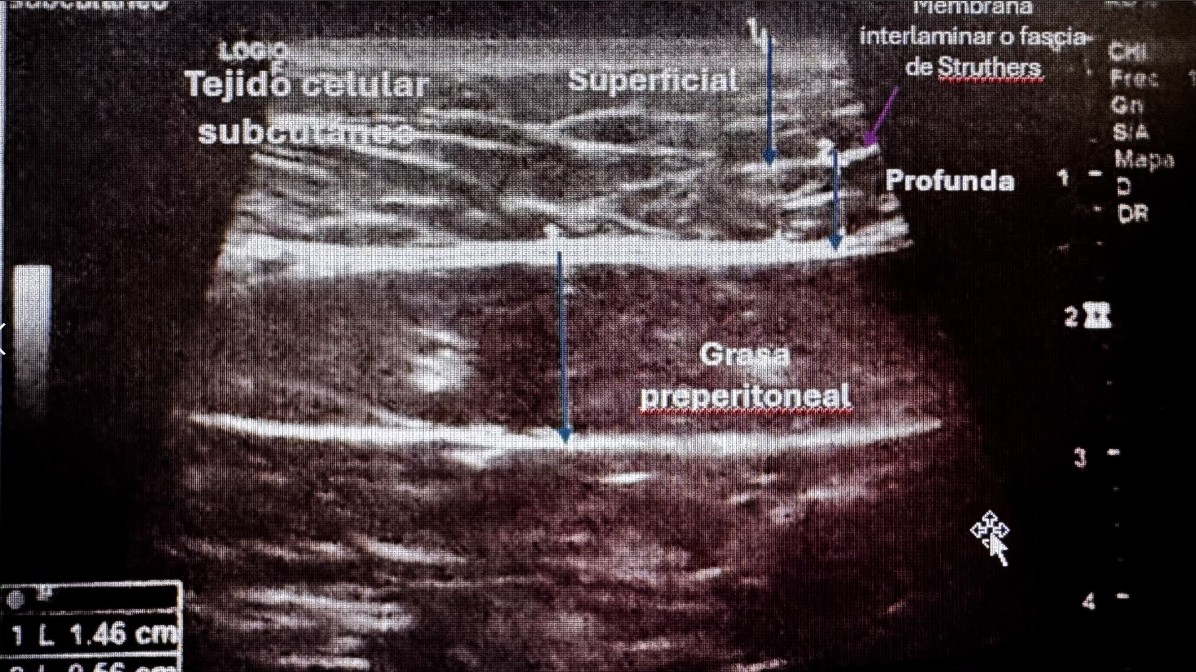

Caso 3. Adiposidad normal en paciente con Riesgo Metabólico. Mujer 43 con Obesidad grado I (32 kg/m2), que inicia tratamiento farmacológico con trizetapide/semanal. Sd metabólico. Glucosa basal y triglicéridos límite, HDL bajo. Ecografía revela distribución adiposa paradójica: grasa subcutánea abdominal normal, con aumento relativo de la grasa visceral preperitoneal (15.8 mm), Intervención: dieta mediterránea. Intervención: dieta mediterránea, ejercicio aeróbico 150 min/semana, seguimiento metabólico. A los 3 meses, ha perdido peso 10 kg y mejoría de perfil lipídoco, pendiente control ecográfico.